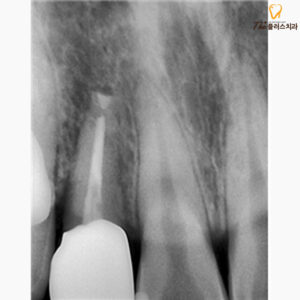

시간이 지남에 따라 통증과

치아의 흔들림이 조금씩 줄어들게 되며,

치아가 자리 잡았고 본을 떠

크라운을 제작해 마무리해 드렸습니다.

환자분께서 치아를 살리려는

의지가 강하셔서 정기적으로 검진도 잘 오셨고,

치아를 살리지 못할 가능성이 많다고

설명을 드리고 진행한 치료였는데

성공적으로 마무리되어 뿌듯한 치료였는데요.

크게 문제가 없고,

통증도 없어져 앞으로도

꾸준히 환자분께서 관리를 잘해주신다면

어려움 없이 사용하실 수 있지만,